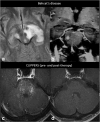

Purpose: Miliary enhancement refers to the presence of multiple small, monomorphic, enhancing foci on T1-weighted post-contrast MRI images. In the absence of a clear clinical presentation, a broad differential diagnosis may result in invasive procedures and possibly brain biopsy for diagnostic purposes.

Results: Miliary pattern of enhancement may be due to a variety of underlying causes, including inflammatory, infectious, nutritional or neoplastic processes. The recognition of disease spread along the perivascular spaces in addition to the detection or exclusion of disease-specific features on MRI images, such as leptomeningeal enhancement, presence of haemorrhagic lesions, spinal cord involvement and specific localisation or systemic involvement, allows to narrow the potential differential diagnoses.